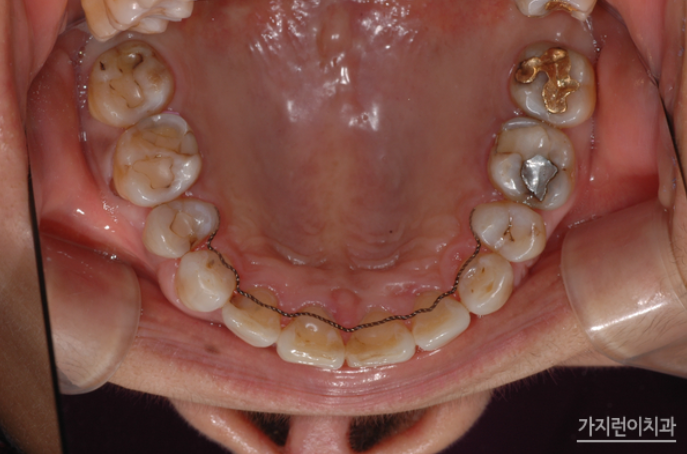

특히 본원에서는 안정적인 교정을 위해 상악 설측교정 장치는 두 개의 와이어를 사용하는 탄댐설측교정을 진행했습니다. 교정과 임플란트를 병행 했음에도 결과를 보면 안정적인 구치부 교합을 만들었다는 것을 확인할 수 있었는데요. 임플란트는 고정이 되기 때문에 교정이 아주 약간만 틀어져도 틈이 벌어지는 등의 문제가 생길 수 있습니다. 그래서 계획대로 치아이동이 잘 되어야 했었는데요. 사진을 보면 지정된 위치에 임플란트가 식립되어 조화로운 치열과 교합 상태로 완성된 것을 볼 수 있습니다.

환자 분은 교정이 끝난 후 꾸준히 정기검진을 받아보고 계신데요. 3년이 지난 날에도 교합이 안정적으로 유지된 것을 확인할 수 있었습니다.